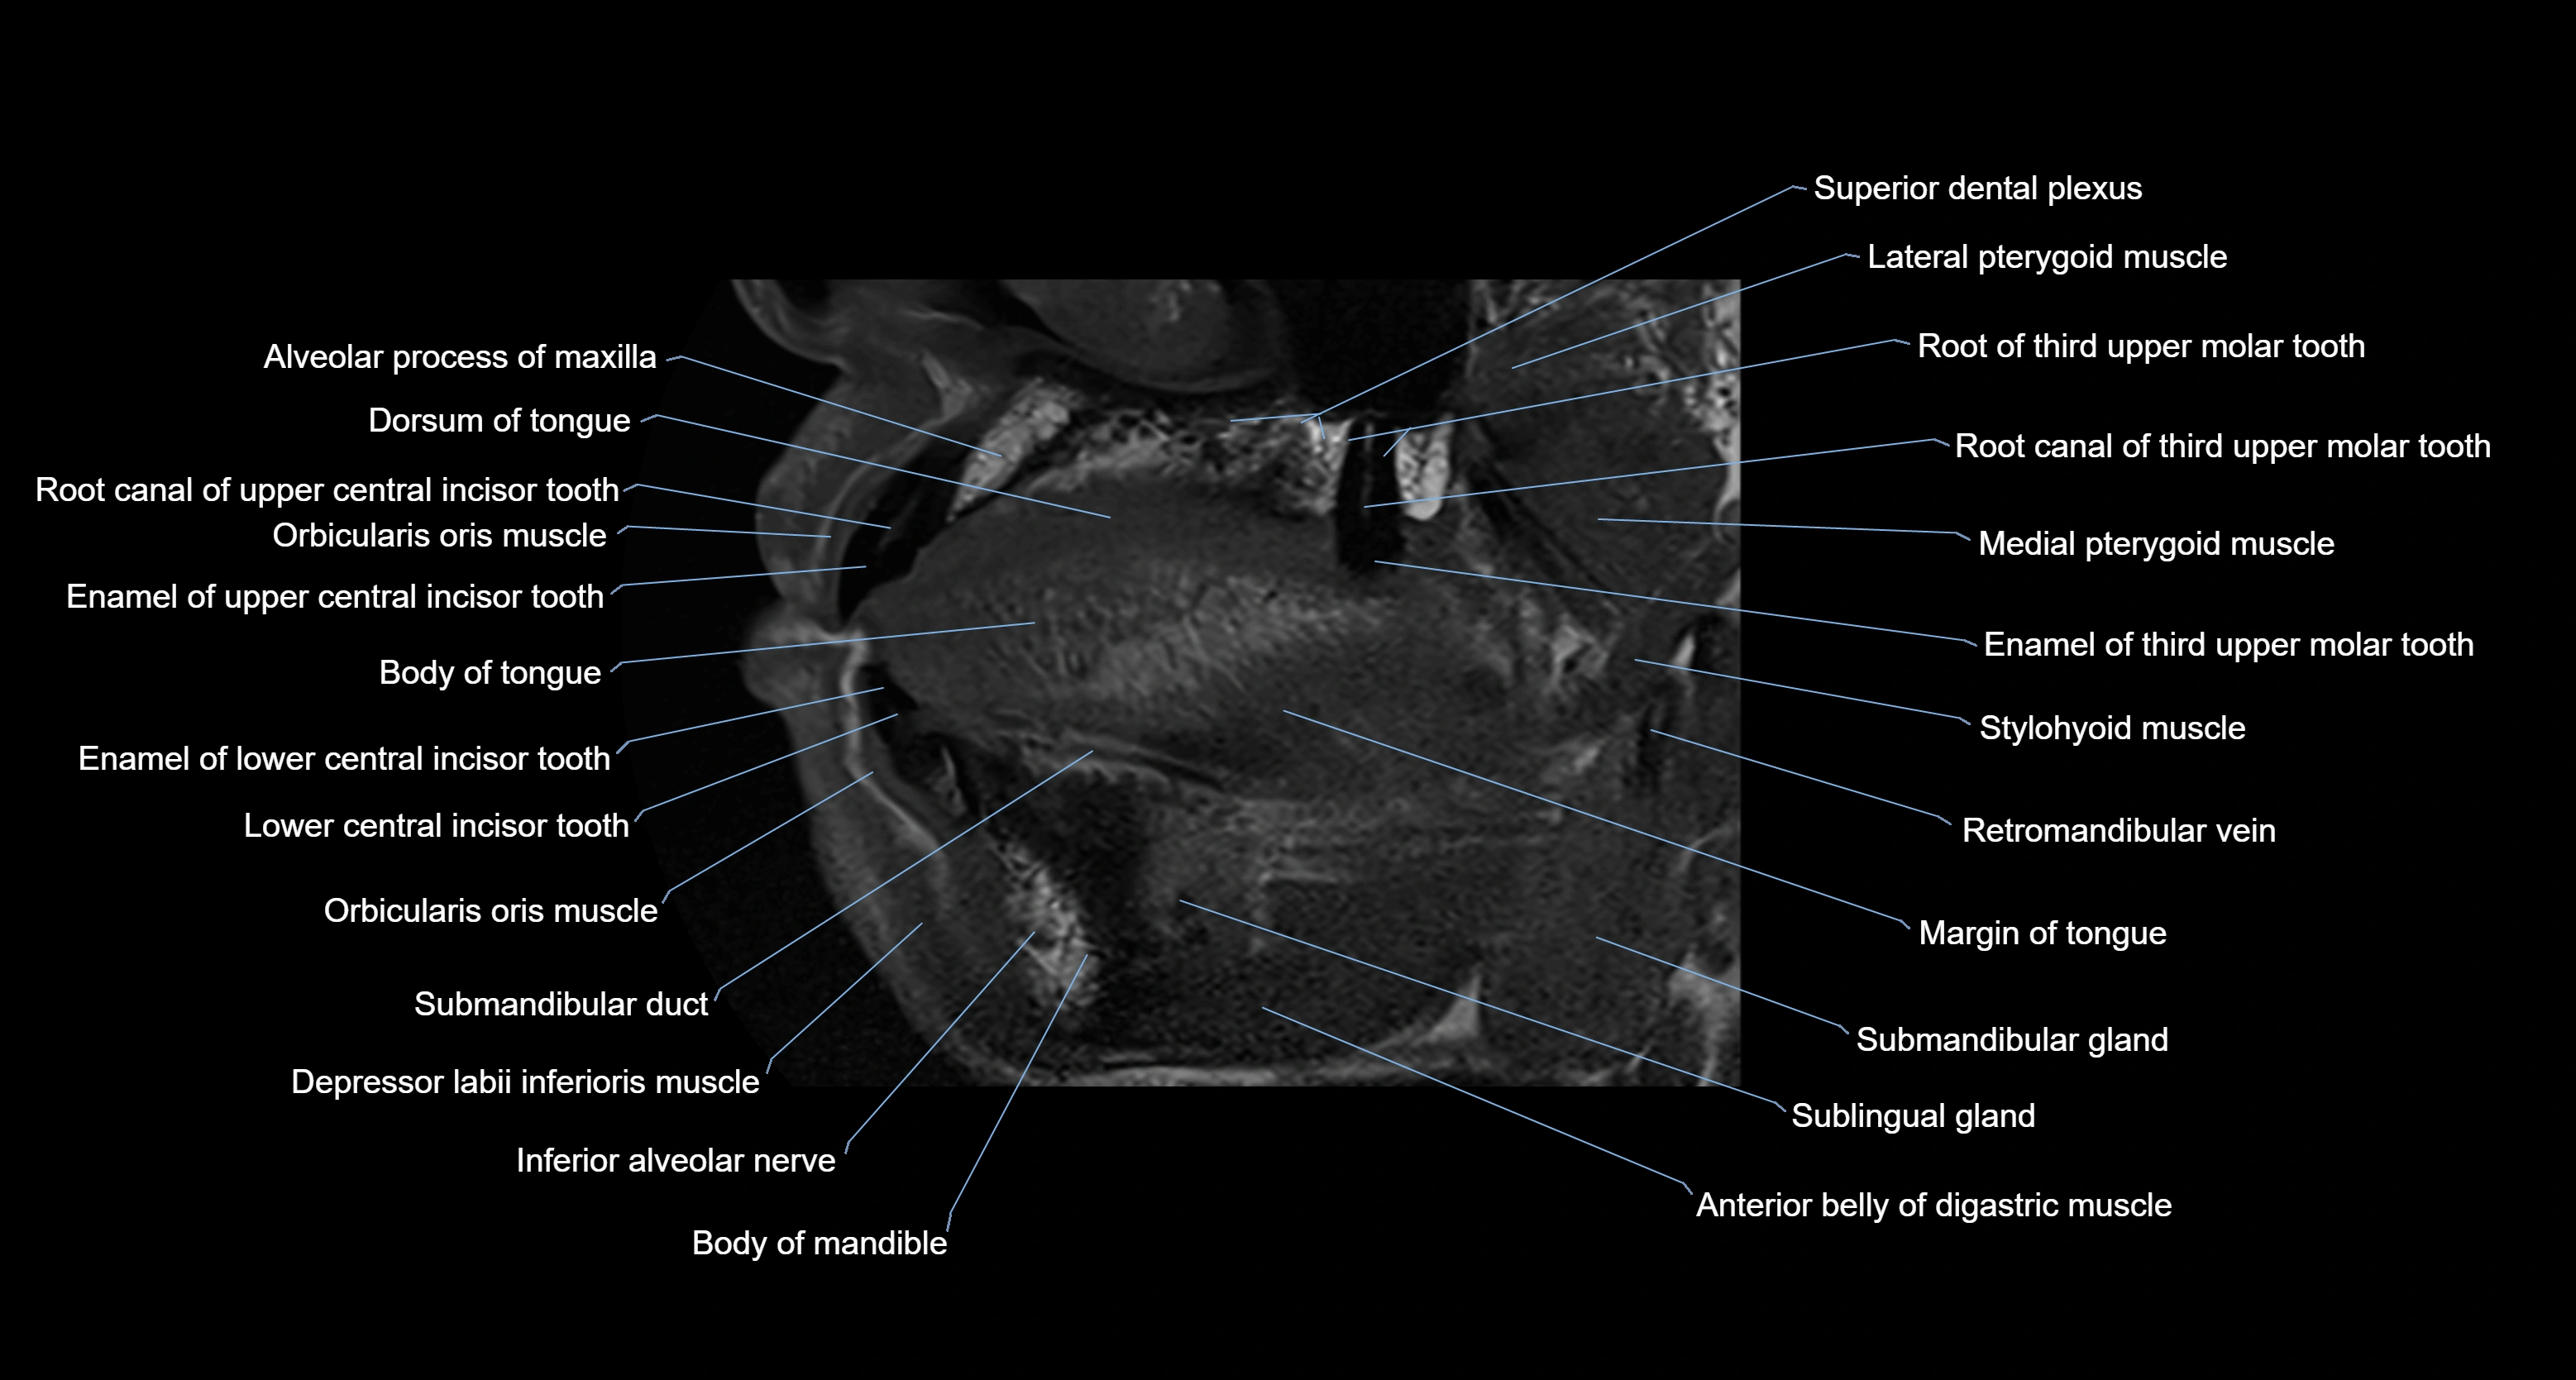

- Body of mandible

- Body of tongue

- Dorsum of tongue

- Inferior alveolar nerve

- Orbicularis oris muscle

- Stylohyoid muscle

- Superior dental plexus